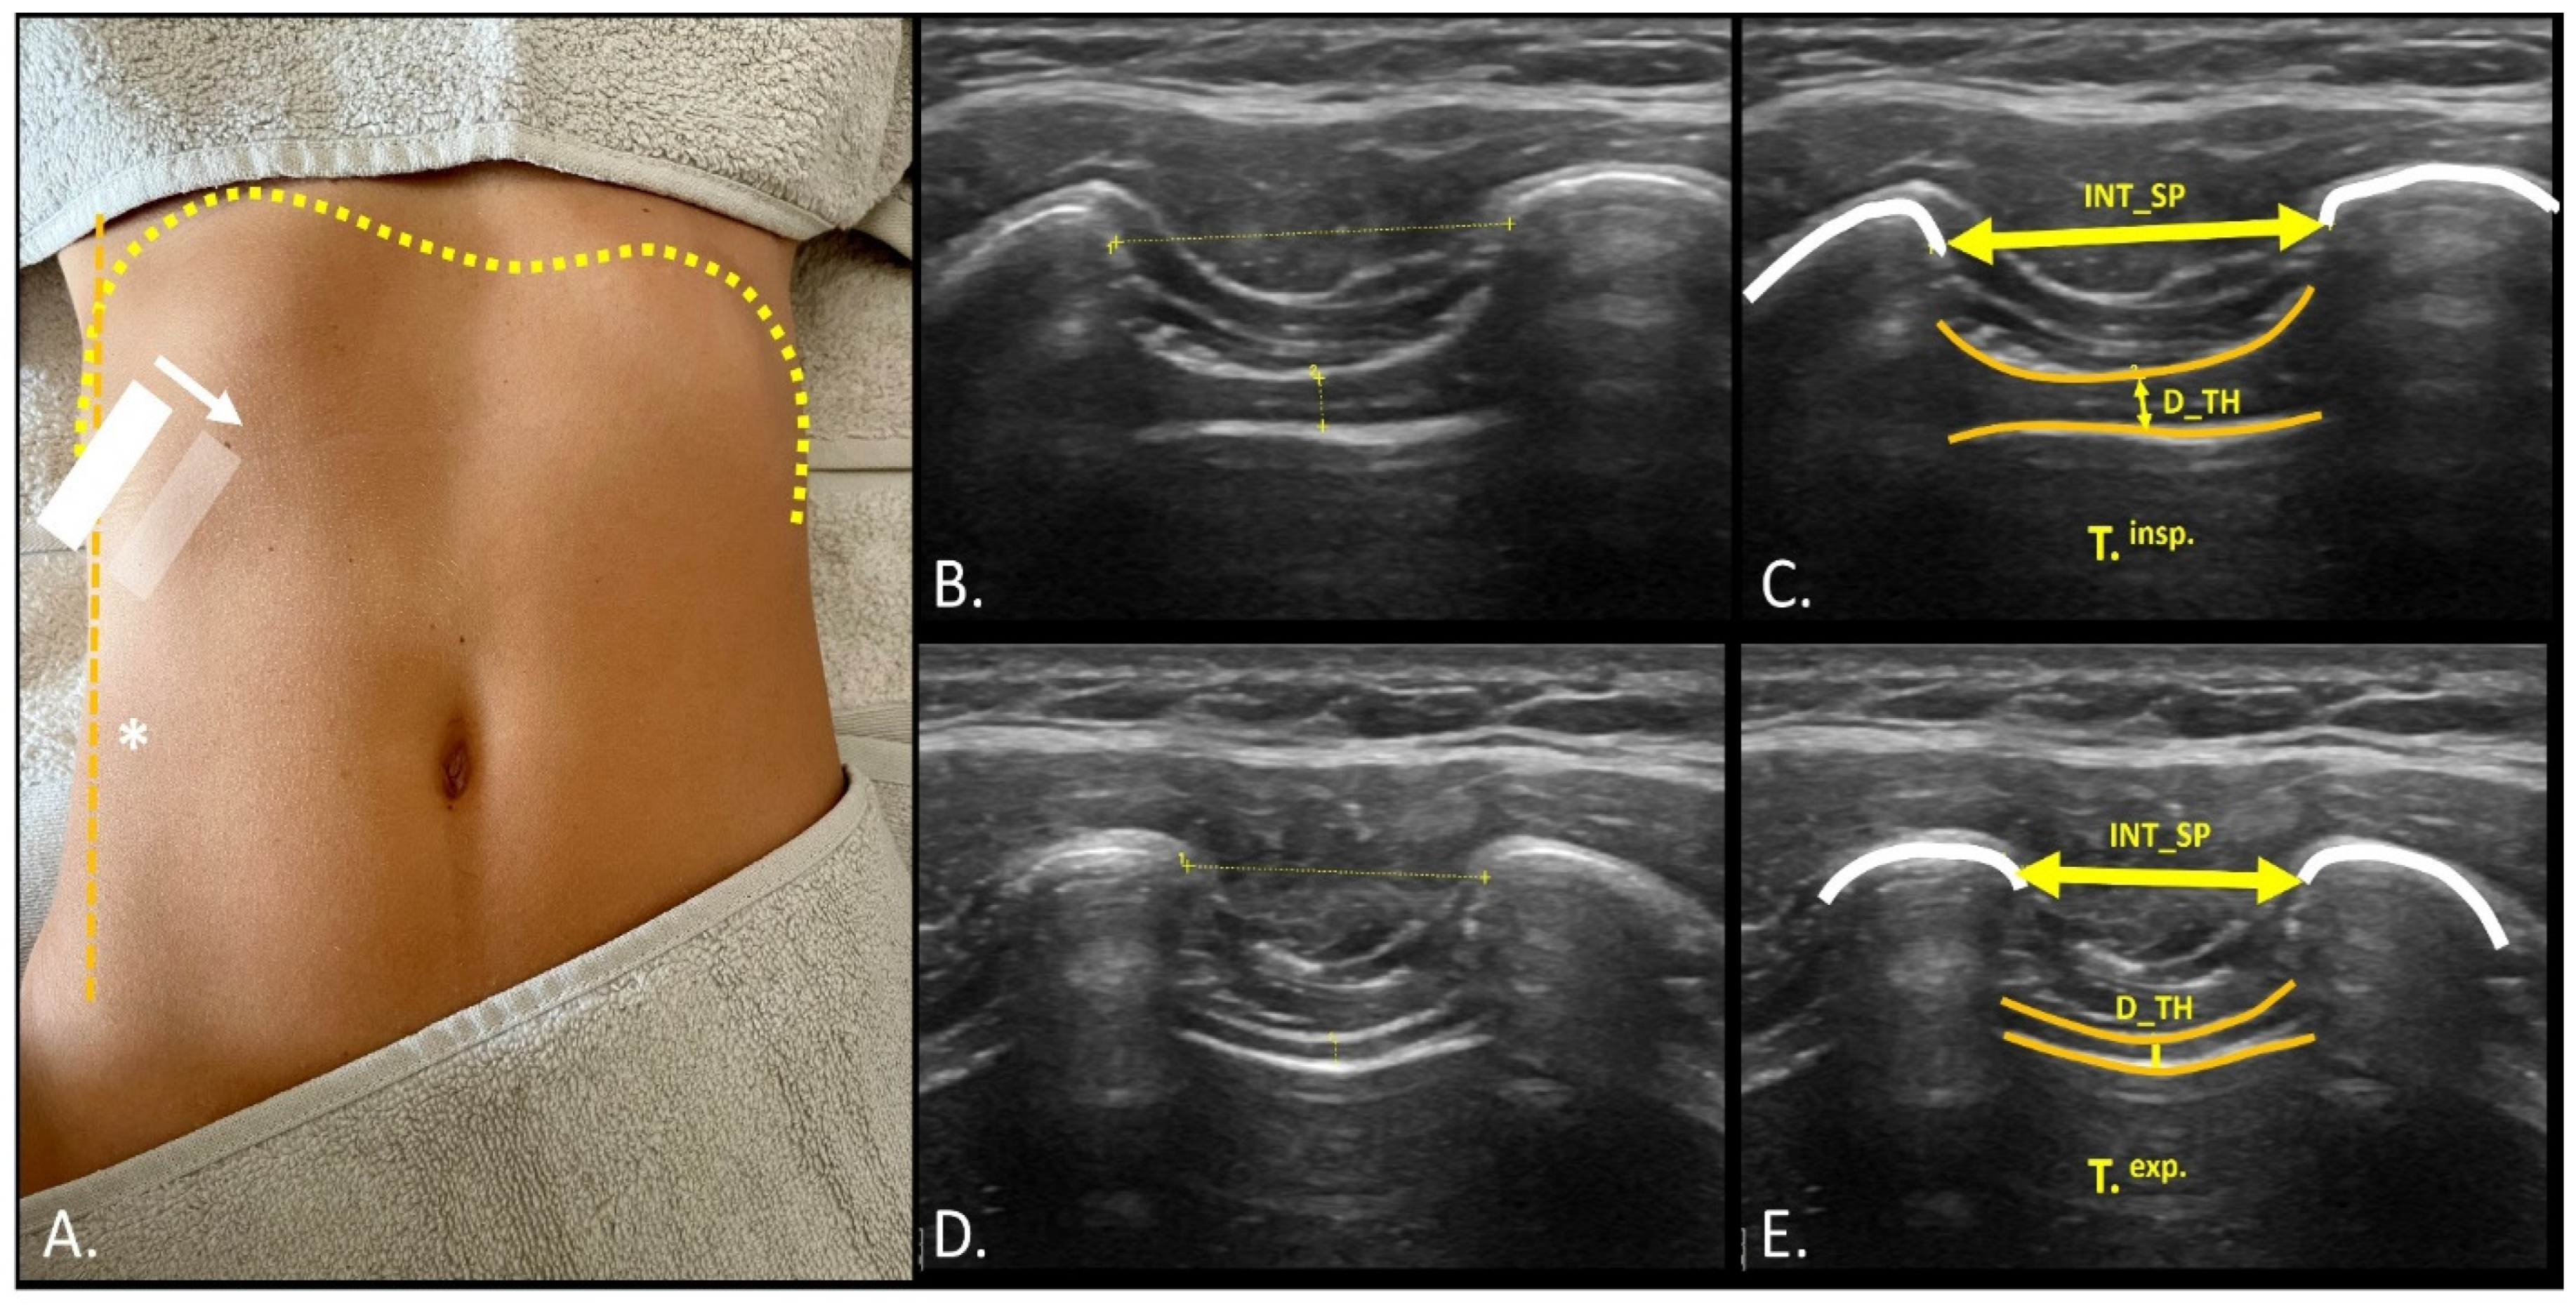

2.4. Sonographic Measurements